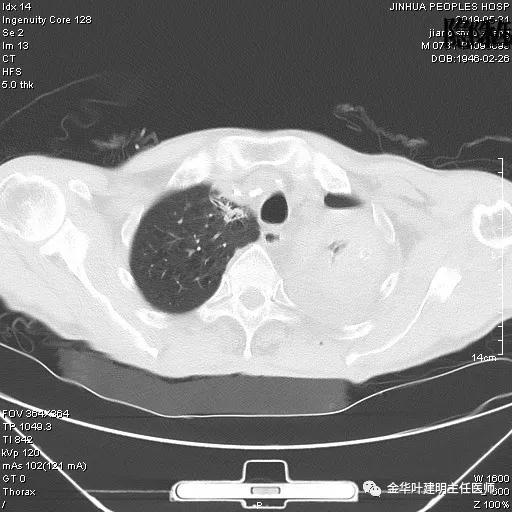

考虑左侧大量胸腔积液,遂进一步胸部CT检查:

以上是肺窗表现,下面为纵隔窗影像: